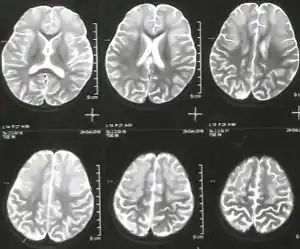

MRI image showing hyperintense lesions in both frontal regions